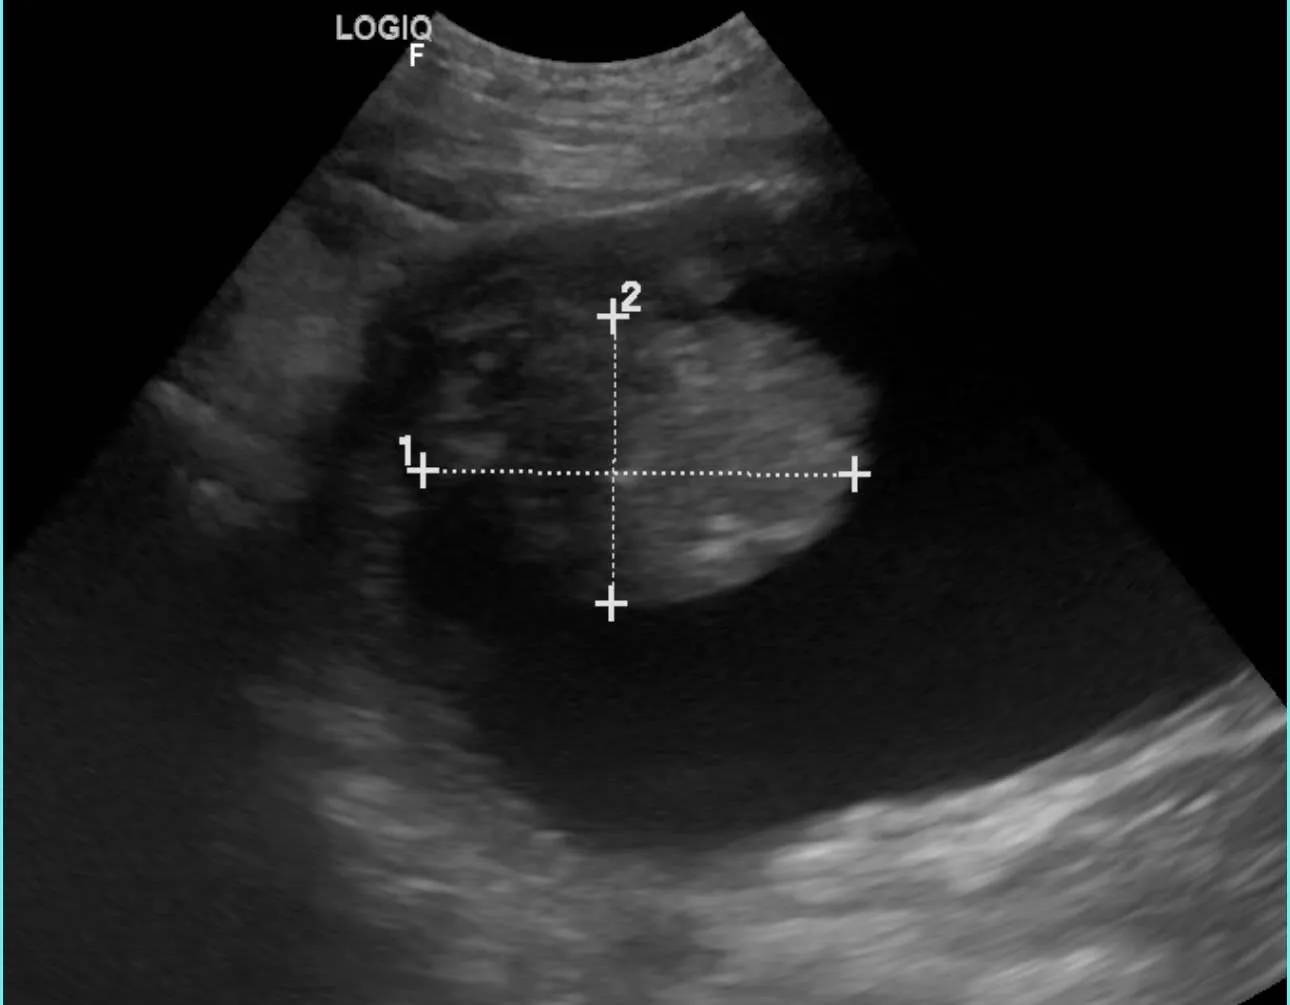

簡單掃個超音波,就能大致區別與排除腫瘤或一般感染、結石的可能性。

膀胱出現明顯腫塊,伴隨血尿、頻尿,在開始口服化療後已明顯改善